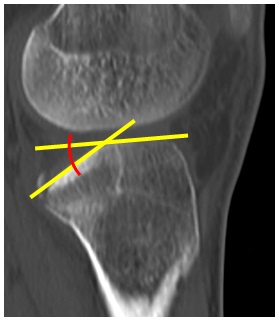

Mediante la observación de los diferentes cortes tomográficos hallamos dos variantes de depresión (TP) de la superficie articular: tipo A, (hundimiento) donde hay un hundimiento circunscripto del platillo en 18 pacientes (66 % en nuestros casos) (Fig. 4), y tipo B, (declinación) impactación del hueso esponjoso con una inclinación hacia posterior del relieve articular en 15 pacientes (Fig. 5).

Figura 5. Declinación. El colapso posterolateral provoca un aumento significativo de la pendiente posterior del platillo tibial.